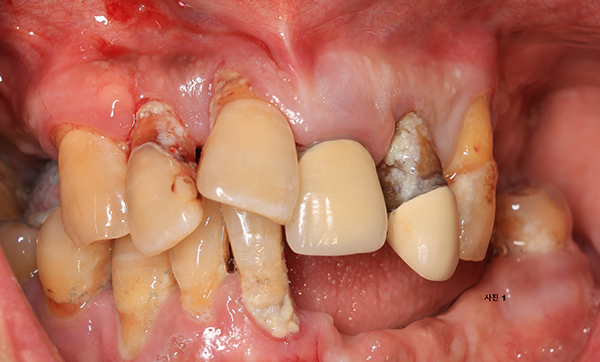

틀니를 상담하기 위해 내원한 50대의 환자로써 (사진1 ) 파노라마사진을 촬영하고 구강검진(사진2) 하여보니,

아직 나이도 젊고 일반 틀니로서는 기능회복이 어려울 것 같아 임플란트를 이용한 똑딱이 틀니를 설명하였다.

그러나 환자가 틀니 대신에 고정성 보철물을 문의하기에 환자의 구강상태, 전신 건강상태, 치료비의 감당능력을

서로 상의하고 상하악에 최소 4개씩 식립하고 풀아치 고정성 보철물을 제작하기로 하였다.